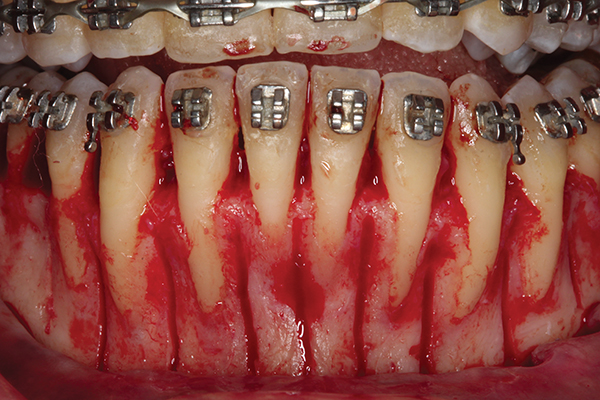

Fig 1. Preoperative SFOT. No loss of attachment, but thin dentoalveolar bone phenotype noted clinically.

Figure 1

Fig 2. Full-thickness flap reflection. Note

dehiscence and fenestrations throughout. Orthodontic walls are limited to nonexistent.

Figure 2

Fig 3. Corticotomy cuts performed.

Figure 3